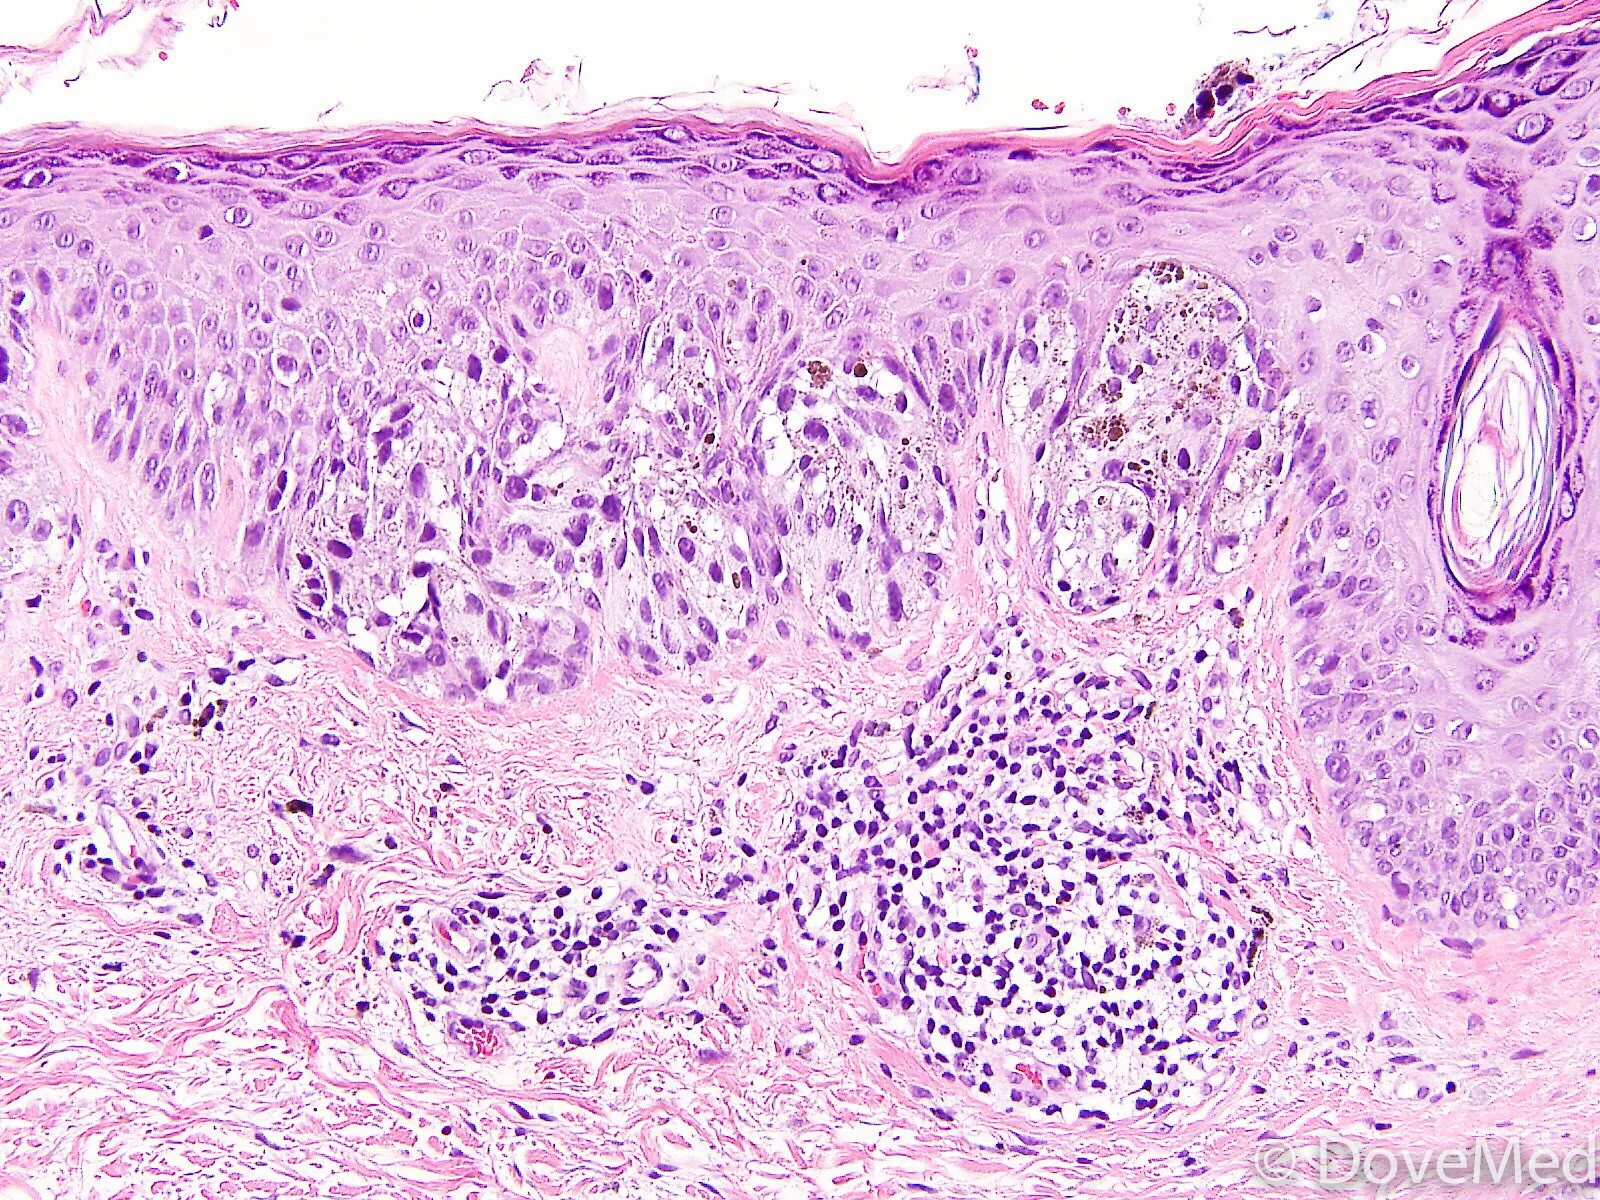

Молекулярная гистология